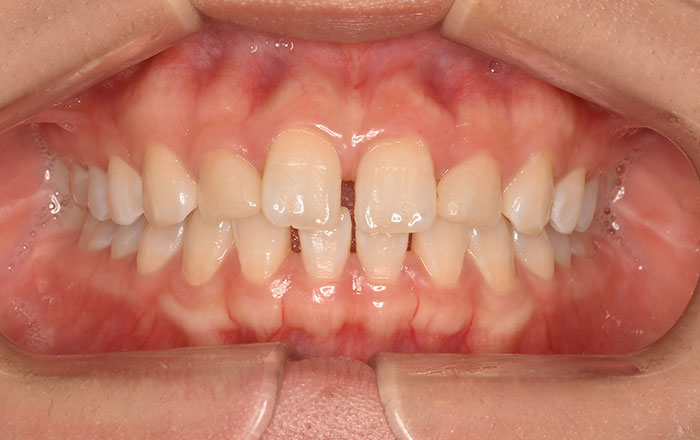

①頬の内側、舌の横に付く歯の痕

②上顎下顎にできる骨隆起

③ほっぺの内側に歯の跡がつく

このような症状があると歯ぎしり、食いしばりをしている可能性があります。